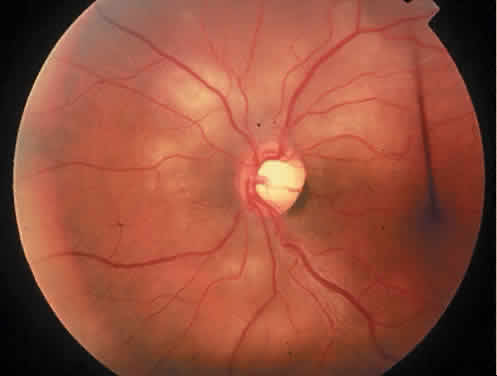

The clinical findings of intraocular lymphoma are variable and usually nondiagnostic. In general, in patients with systemic NHL and intraocular NHL, the extent of intraocular involvement tends to parallel the severity of systemic involvement.95 Additionally, the long-term survival of patients with intra-ocular involvement from systemic NHL is poor.Patients with systemic NHL are more likely to haveuveal infiltration, whereas those with NHL-CNS generally present with vitreous infiltration.96,97 Most patients present with posterior uveitis or vitritis, but anterior uveitis and optic nerve involvement may occur.94 Other less common manifestations of intraocular lymphoma include retinal vasculitis,98 central retinal artery obstruction,99 and solitary lesions, which resemble acute retinal necrosis.100 Anterior uveitis causing episodes of elevated intraocular pressure also has been reported with NHL.101 Typically, distinctive yellow or white subpigment epithelial masses are thought to be virtually pathognomonic (Fig. 13), but nonspecific peripheral pigment changes may occur. The clinical course often is one of chronic uveitis that is poorly responsive to steroid therapy. Because of the usually nonspecific clinical findings, intraocular lymphoma should be considered in the differential diagnosis of any posterior uveitis in middle-aged individuals. Unfortunately, the diagnosis often is missed, as evidenced by the high percentage of diagnoses made at autopsy.94

Fig. 13. Lesions typical of subpigment epithelial intraocular lymphoma. (Gass JDM, Sever RJ, Gizzard WS et al: Multifocal pigment epithelial detachments by reticulum cell sarcoma. Retina 4:136, 1984.)